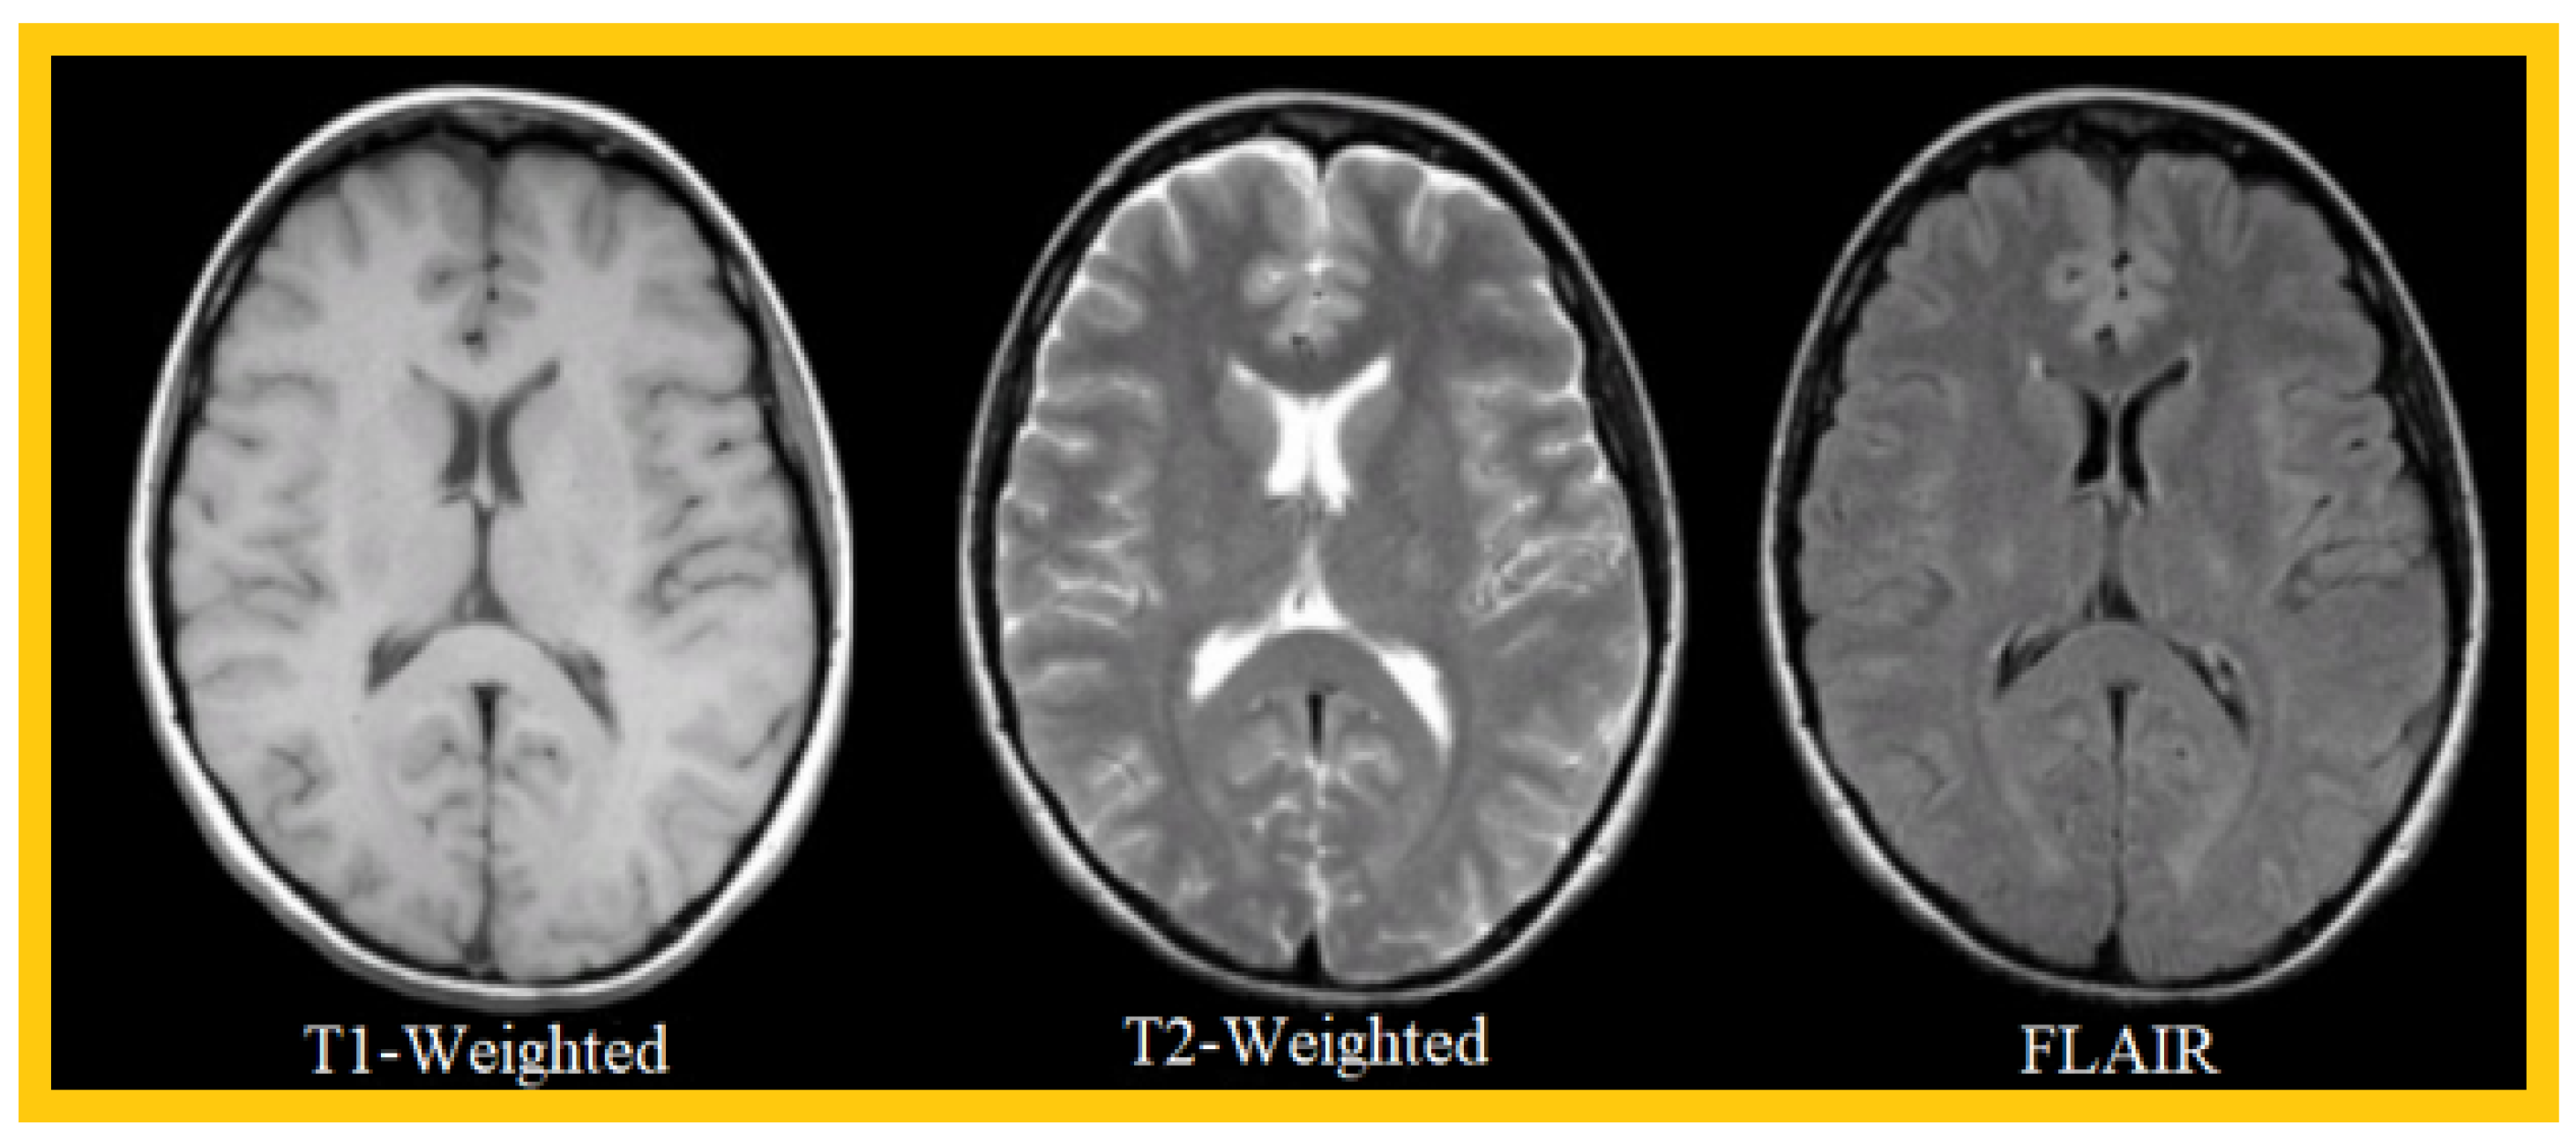

1.2. MRI Sequences for Brain Tumors